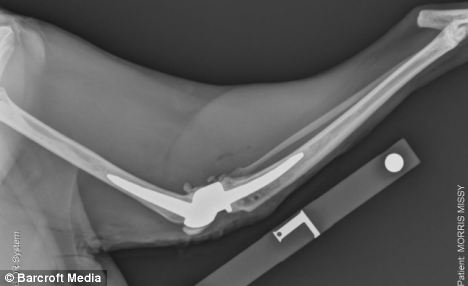

X光掃描顯示人造膝蓋的位置